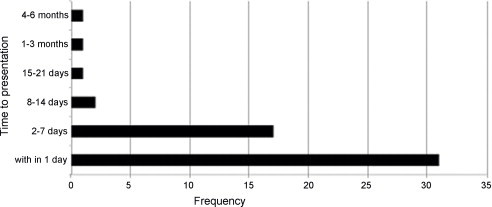

When we scanned for the literature concerning anorectic foreign objects, no case report was found for anorectal bodies that remained for 5 years in the rectum. According to the 2010 review of Kurer et al., 58.5% of cases were consulted on the same day and 32.1% 2–7 days after the incident for 53 cases in emergency services. Just one patient waited for 6 months after the incident (Fig. 4).8 In our case, a 22 years old patient came for consultation 5 years after the initial incident, which occurred when he was 17 years old.

Fig. 4.

Time interval between insertion of foreign body and presentation for treatment in single case reports (n = 53) Kurer et al.